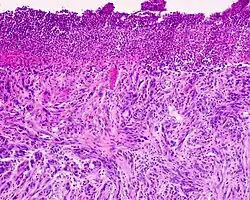

Desmoplastic melanoma, also known as neurotropic melanoma, or spindled melanoma[1] is a rare cutaneous condition characterized by a deeply infiltrating type of melanoma[2]: 696  with an abundance of fibrous matrix. It usually occurs in the head and neck region of older people with sun-damaged skin. Diagnosis can be difficult as it has a similar appearance to sclerosing melanocytic nevi as well as some nonmelanocytic skin lesions such as scars, fibromas, or cysts. Desmoplastic melanomas tend to recur locally, with distant metastasis being less common.[3]